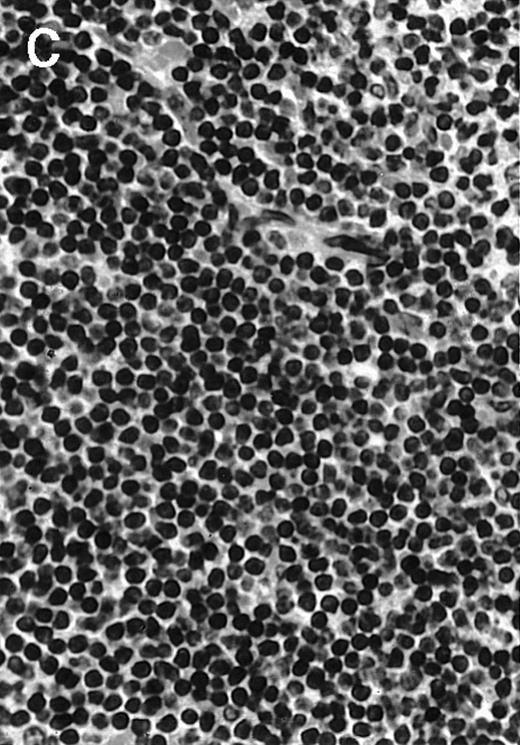

To analyze expression of the human CD40L protein in murine tissues, samples from the small intestine, colon, liver, and spleen were analyzed by HE staining as well as immunohistochemistry. We found that in mice immunized with ST40L, the Peyer's patches were prominent (Figure 1A), and the majority of cells in the Peyer's patches could be seen to express the human CD40L protein (positive: brown or yellow color; negative: blue color) (Figure 1B). There were a few CD40L+ cells in spleen, but not in liver. In contrast, human CD40L was not detectable in the Peyer's patches of mice treated with ST (Figure 1C). To further confirm the secretion of human soluble CD40L by transfected murine cells into the sera, we next examined it by ELISA (Figure 2). Human soluble CD40L protein was detectable only in BALB/c mice treated with ST40L with or without administration of BCL cells, but not detectable in mice treated with ST and/or BCL cells. The level of soluble CD40L protein in the sera peaked at 1 week after oral administration and was detectable until 7 to 8 weeks.

Presence of transduced human CD40L protein in mice treated with ST40L.

(A) HE staining of intestine ( × 100) of BALB/c mice killed 1 week after oral administration of ST40L. (B) Immunostaining of Peyer's patches using antihuman CD40L Ab (×400) of BALB/c mice killed 1 week after oral administration of ST40L. (C) Immunostaining of Peyer's patches using antihuman CD40L Ab (×400) of BALB/c mice killed 1 week after oral administration of ST.

To explore the mechanisms of the protection from BCL growth, histologic analysis was performed on tumor tissue from mice treated with ST40L, ST, or PBS alone. In the mice treated with PBS alone, no cellular infiltrate expressing FasL was observed in the surrounding tissues and inside the BCL region (Figure 4A and D). In contrast, infiltrating lymphocytes expressing FasL were observed around the vessels and also scattered in the smaller tumor tissues in the mice treated with ST (Figure 4B and E). Small hard nodules (2-5 mm in diameter) were observed at the SC injection sites of the long-term survival mice that had been treated with ST40L. On histologic analysis, these small nodules were confirmed to be the result of an accumulation of lymphocytes, and not BCL cells (Figure 4C). These lymphocytes were also found to be strongly positive for FasL expression (Figure 4F). On the other hand, lymphocytes infiltrating in the nodules were stained by either CD4+ Ab or CD8+ Ab, but the ratio of CD4+ and CD8+ cells was not 1-sided (data not shown).

Histologic analysis of A20 tumors excised 21 days postchallenge from BALB/c mice immunized with ST40L.

(A) HE stain of a BCL region in a mouse treated with PBS alone. (B) HE stain of a smaller BCL region in a mouse treated with ST. (C) HE stain of a small hard nodule at the SC injection site in a mouse treated with ST40L. (D) Fas ligand staining of a BCL region in a mouse treated with PBS alone. (E) Fas ligand staining of a BCL region in a mouse treated with ST. (F) Fas ligand staining of a small hard nodule at the SC injection site in a mouse treated with ST40L. Original magnifications are ×400.